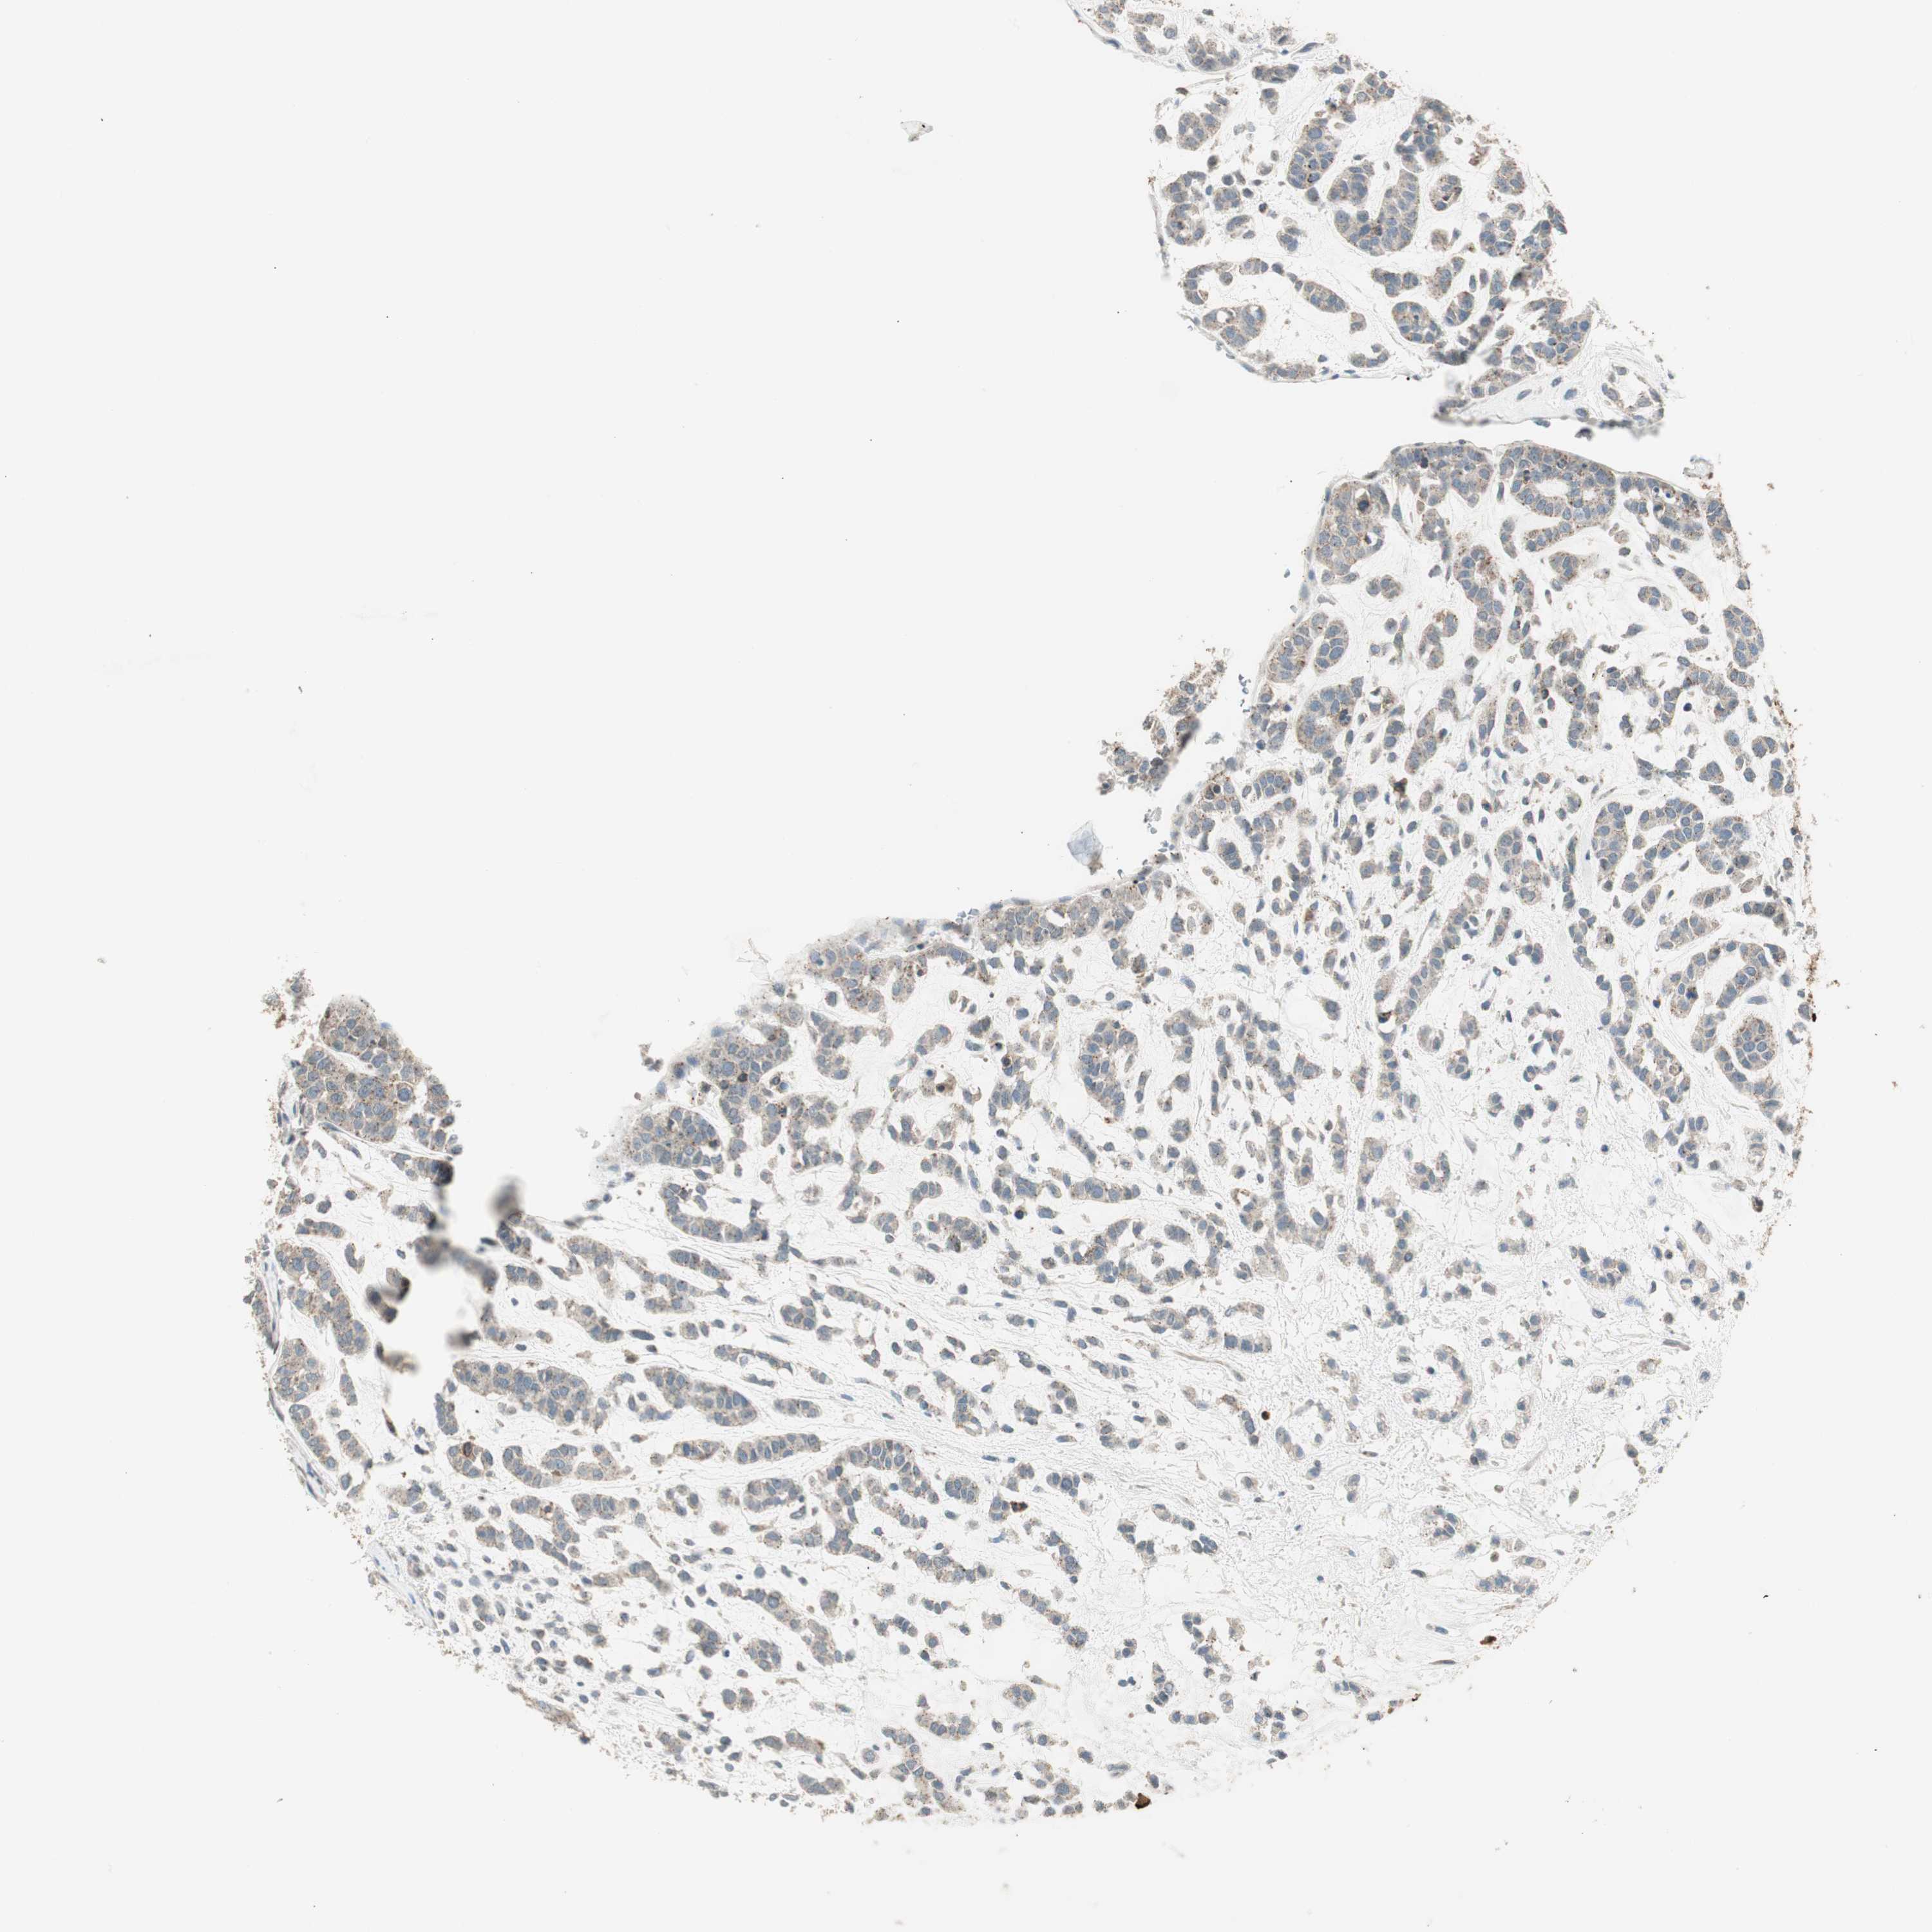

HEAD AND NECK CANCER - Protein expressioni

A mouse-over function shows sample information and annotation data. Click on an image to view it in a full screen mode. Samples can be filtered based on level of antibody staining by selecting one or several of the following categories: high, medium, low and not detected. The assay and annotation is described here.

Antibody stainingi

Antibody staining in the annotated cell types in the current human tissue is reported as not detected, low, medium, or high, based on conventional immunohistochemistry profiling in selected tissues. This score is based on the combination of the staining intensity and fraction of stained cells.

Each image is clickable and will lead to virtual microscopy that enables deeper exploration of all samples and also displays staining intensity scores, fraction scores and subcellular localization as well as patient and tissue information for each sample.

Antibody CAB015221

Adenocarcinoma, NOS

Adenoma, NOS